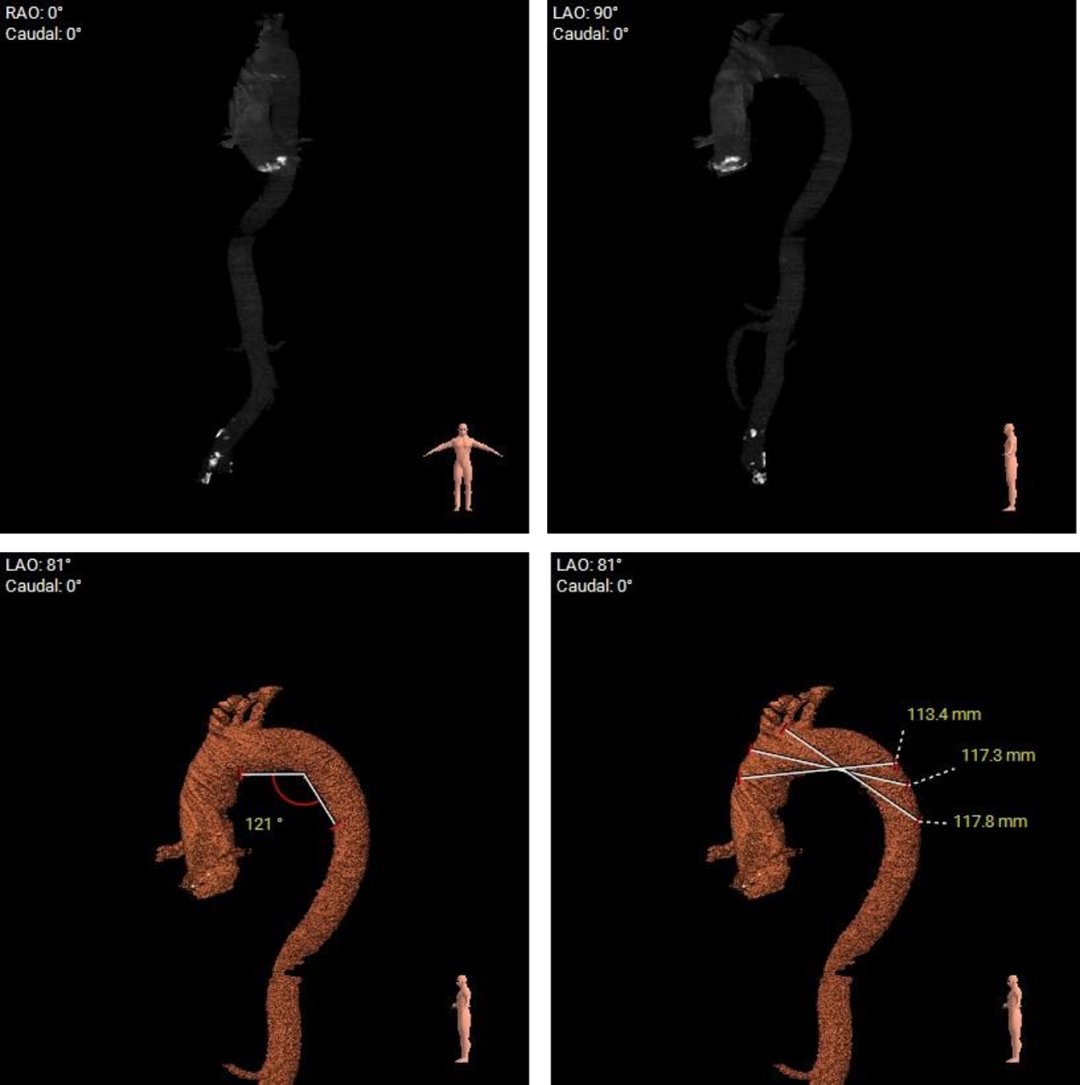

5.主动脉瓣环与水平面夹角为40° ,主动脉弓部夹角及弓距尚可;

主动脉根部测量

瓣上结构测量

本例患者为主动脉瓣中重度狭窄伴中度反流,患者伴心衰、冠状动脉粥样硬化、扩张性心肌病及脑梗等基础疾病,无法耐受外科开胸手术,术前评估适宜行TAVR手术,有TAVR手术指征。术前CT分析提示患者为Type1型二叶式主动脉瓣,瓣环径较大,达到28.1mm,瓣叶轻度增厚伴重度钙化,瓣上限制较重左右窦瓣叶交合缘可见钙化融合剂,给瓣膜的锚定增加了较大的难度,瓣膜植入后存在形变、移位和瓣周漏的风险。患者为非横位心,升主动脉内径可,输送系统可顺利过弓、跨瓣。此外,该患者全心扩大,EF值为45%,术中循环崩溃风险适中,对术者快速、精准的操作能力及手术团队的密切配合要求较高。